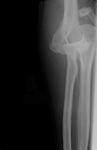

Incidência anteroposterior de radiografia de luxação do cotovelo

Acervo pessoal do Dr. Paul Novakovich

Incidência anteroposterior de radiografia de luxação do cotovelo reduzida